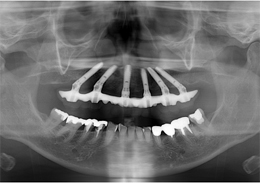

- 主訴

- もともと入っているインプラントの周りが腫れ、残りの歯も動いているので力が入らない

- 治療内容

- 下顎右側に以前埋入したインプラントの撤去を行い、歯周病の進行が著しかった残存歯の抜歯を行うと同時にインプラントの埋入を行い、当日仮歯を装着した

- 治療費用

- 下顎ALL-ON-4:4,000,000円(税別)

- 治療期間

- 6ヶ月